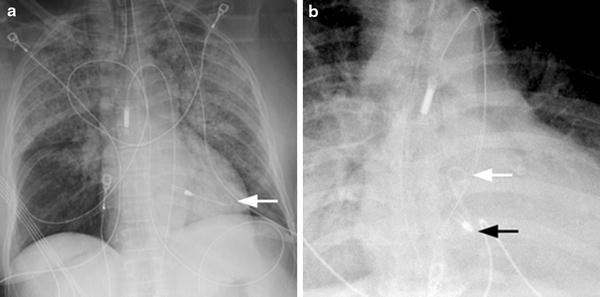

Two Cases Of Successful Treatment Of Acute Right Heart Failure With Impella Rp Santer 2020 Esc Heart Failure Wiley Online Library from onlinelibrary.wiley.com Arrows pointing to an impella® heart pump. Robert frankel, director of the cardiac catheterization lab at maimonides medical center. Impella device kit with placement guidewire 3. An overview of the impella device narrated by dr. (wireframe or wireframe+xray works tho if it helps) to reproduce steps to reproduce the behavior the devs already know about xray not working with optifine, sadly the only thing you can do is use it. Name the device • xray of the week cxr for chf. 500 ml bag of 5% dextrose in water with 25 u/ml heparin 4. Name the cardiac device and what the 2 2.

Impella device kit with placement guidewire 3. Name the device • xray of the week cxr for chf. Я уж давно не усатый)) рад. Robert frankel, director of the cardiac catheterization lab at maimonides medical center. The impella's inlet is placed in the left ventricle, where blood is apirated and delivered to the outlet which is situated in the ascending aorta. 500 ml bag of 5% dextrose in water with 25 u/ml heparin 4. An overview of the impella device narrated by dr. 4 or 5 fr pigtail catheter or al 1 or mp. (wireframe or wireframe+xray works tho if it helps) to reproduce steps to reproduce the behavior the devs already know about xray not working with optifine, sadly the only thing you can do is use it. Name the cardiac device and what the 2 2. Arrows pointing to an impella® heart pump.